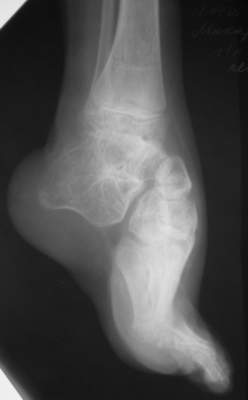

Уважаемые коллеги,Ребенок, мальчик, 11 лет...Врожденная косолапость,до 4 лет лечился консервативно, в 4 года оперирован у нас - операция по типу Зацепина, далее аппаратИлизарова...Предоперционная картина - как на рис "case 1 a" (фото другогобольного)...При операции использовался аппарат с "моноблоком" стопы -см. "case 1 b" (фото другого больного) -в связи с чем интраоперационно провели достаточно выраженную одномоментнуюкоррекциюпосле чего возник некроз в областиоперационных ран в результате чего "вывалился" "кусок" по внутреннейповерхностих...аппарат сняли... больного перевели в отделениемикрохирургии... с другой голени делали пересадку... прижилось...больного выписали...все это было 7 лет назад...3 года назад больной лечился в Астрахани...Никаких выписок нет (не видел...)(хэллоу, астраханцы!!! если есть - отзовитесь...),но со слов мальчика и его матери ему делали удлинение на уровневерхней трети голени плюс исправляли стопу... опять-таки со слов -сразу же после коррекции стопу загипсовали на 6 нед, после чегопрописали ночные тутора плюс ортообувь... т.е. после коррекции стопу ваппарате не выдерживали и гипсовали всего 1,5 мес.... через 6 месстопа "ушла" в исходное положение...с которой он пришел к нам сейчас... (case 2-9)В настоящее время у мальчика эквино (!!!)-варус... в подтаранномсуставе полный анкилоз... (см. Ro)Были предложения исправить деформацию аппаратно с остеотомией черезладью...Передумали:-)...Лично у меня возникают также вопросы на счет плюсне-клиновидныхсусутавов... и так я их Ro-фировал, и эдак (снимки не представлены), авсе равно не могу избавиться от впечталения, что и в них имеется некоефиброзно-костное анкилозирование...А на КТ у больных денег нету...Короче...Наложили аппарат...Попытаемся растянуть стопу + "подкоррегировать" варус иубрать эквинус...А после этого определиться с уровнем остеотомии (это официальноемнение...)Я же хочу сделать все тоже, за исключением остеотомии (при условии чтонет того самого анкилозирования на уровне плюсне-клиновидныхсусутавов...)Убрать варус и эквинус на фоне удлинения...коррекция с гипер-...плюс подержать в этом положении 1-1,5 мес...Но не лежит рука к остеотомии...Единственное, после коррекции есть желание "отсепарировать" подошвенные связки с костной "основой" от пяточной кости и загипсовать в таком положении во избежание возможного рецидива...А там посмотрим...мнения ???